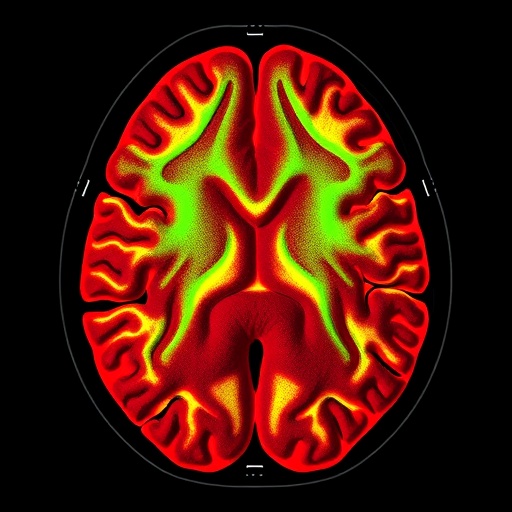

Using state-of-the-art MRI technology, the study meticulously quantified different body compartments. This detailed analysis not only allowed for precise measurements of muscle and fat distribution but also enabled the researchers to explore how these compartments affect metabolic functions. The results reveal intricate relationships where not only the amount of fat or muscle plays a crucial role but also their specific distribution across the body impacts metabolic health.

The incorporation of advanced imaging technology such as MRI illustrates not only the potential for enhanced data collection but also the importance of multidisciplinary approaches in modern health research. By fusing together disciplines such as genetics, immunology, and radiology, researchers can create a more comprehensive picture of human health, which may transform how we approach disease prevention and treatment.

Article Title: Magnetic resonance imaging quantifies causal body compartment effects on metabolic traits via immune phenotypes—a Mendelian randomisation study.

Image Credits: AI Generated